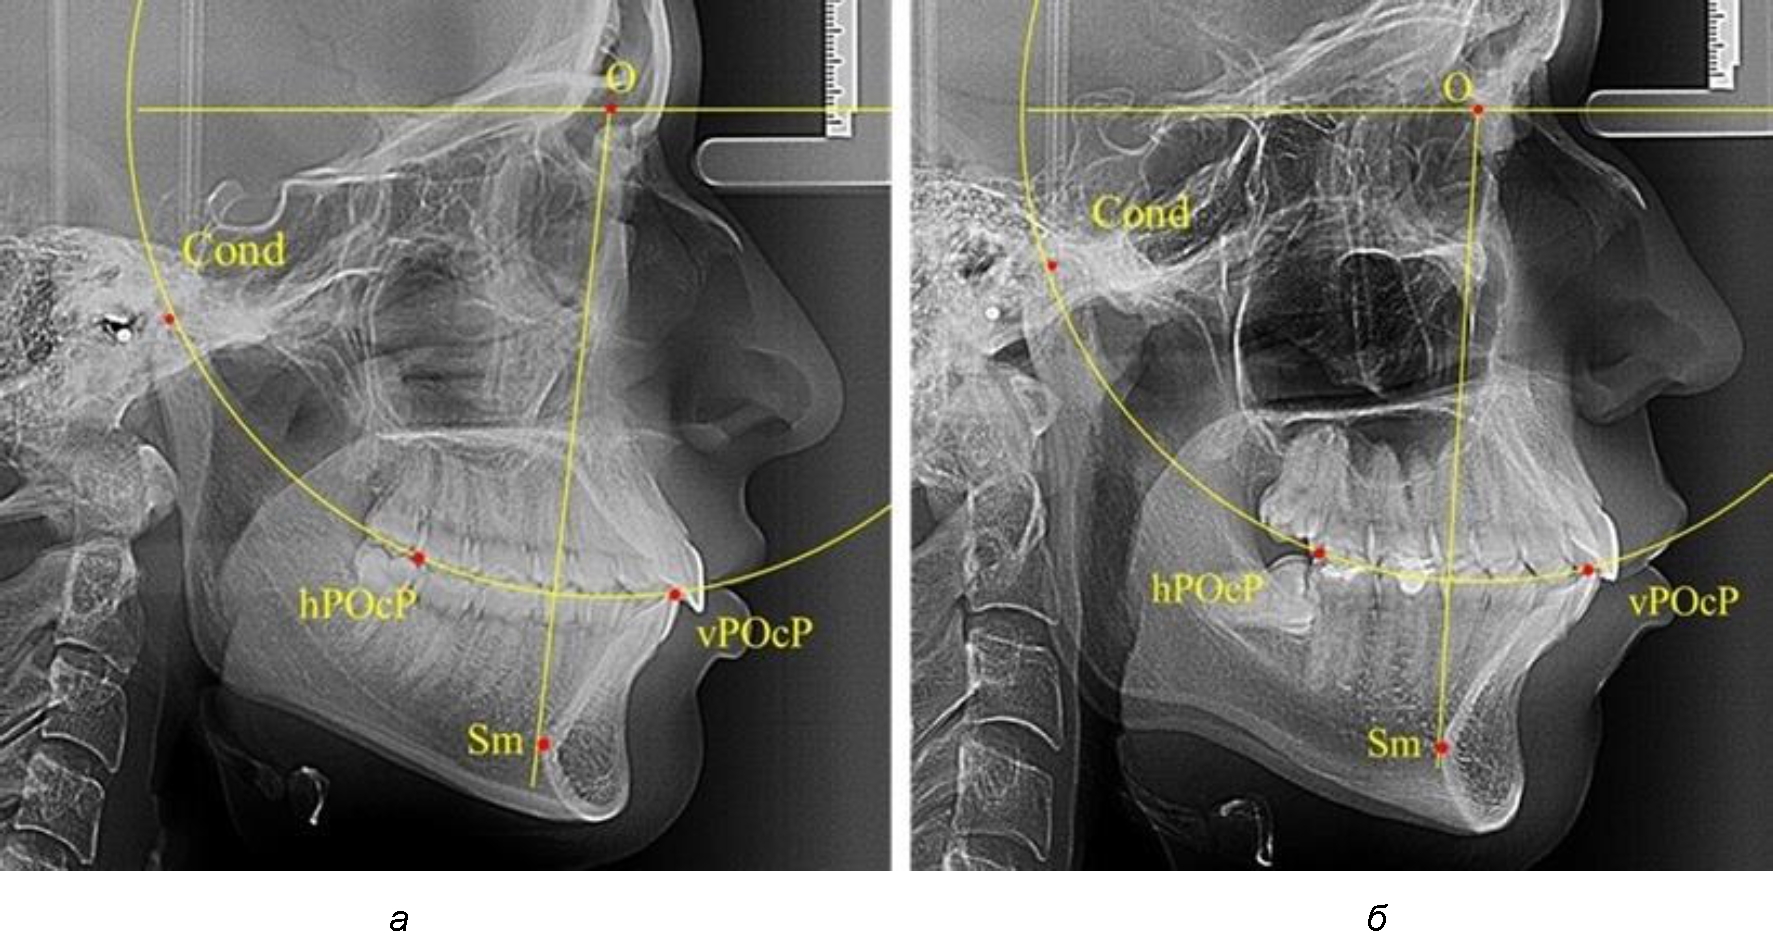

В группе рентгенограмм, выделенных по признаку протрузионного положения резцов, также проводилось распределение на подгруппы с учетом широтных размеров подбородочного выступа.

Анализ результатов показал, что практически при всех вариантах подбородочного выступа в данной группе исследования первые премоляры, как правило, располагались впереди стресс-оси Bimler. Рентгенограммы пациентов с протрузионным положением резцов при среднем и узком варианте подбородочного выступа представлены на рис. 3.

Таким образом, для людей с протрузионным типом зубочелюстных дуг характерно расположение первых премоляров впереди стресс-оси, и этот показатель не может быть использован в качестве выбора метода лечения аномалий для данной группы исследования вне зависимости от формы подбородочного выступа.

Рис. 3. Положение первых верхних премоляров при протрузии со средними (а) и узкими (б) размерами подбородка